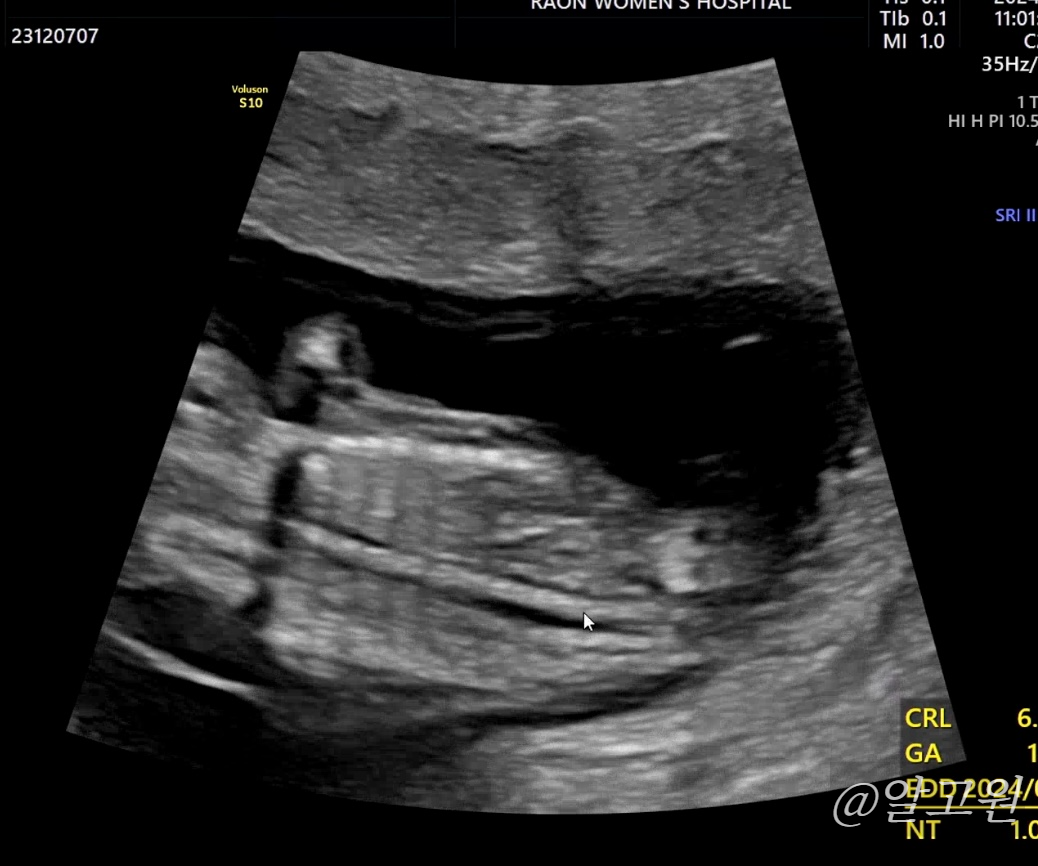

초음파로 목투명대, 척추와 뼈, 장기, 뇌 모양, 심장박동소리, 태반 위치 등

선생님께서 아주 꼼꼼히 봐주십니다.

다행히도 유동이는 정상,정상,정상!

목투명대도 1mm로 정상수치에 들었어요.

(3mm 이하면 정상, 이상일 경우 추가 검사진행)